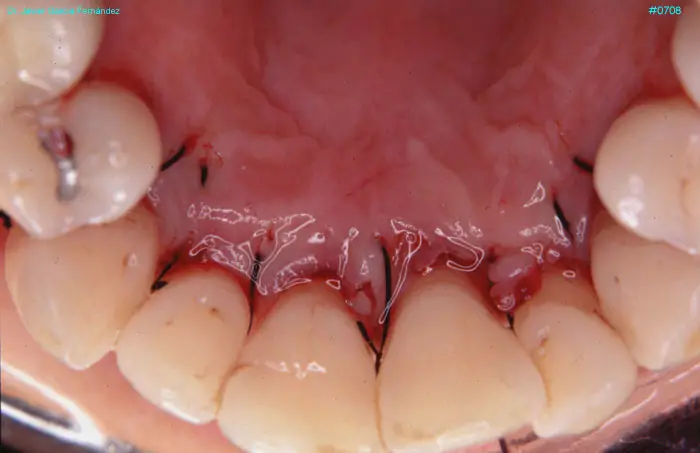

Atlas of Surgical Techniques in Periodontics. Chapter III. Atlas de Técnicas Quirúrgicas en Periodoncia